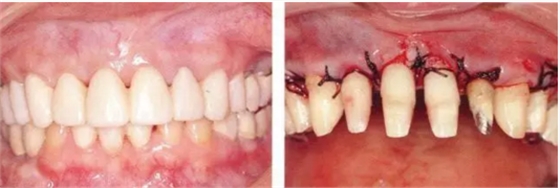

▲圖19-8,9

▲圖19-8 佩戴臨時修復體。即使在這個狀態(tài)下,依然有牙周袋殘留。

▲圖19-9 完成牙周外科治療后的狀態(tài)。

▲圖19-10,11

▲圖19-10 牙周外科治療后3周的狀態(tài)。從照片可見牙周袋的去除量。

▲圖19-11 數(shù)月以后,對臨時修復體進行修整后的狀態(tài)。